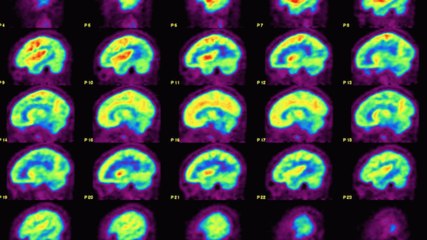

Neuroplasticity: How to Rewire our Brains with Neuroplasticity